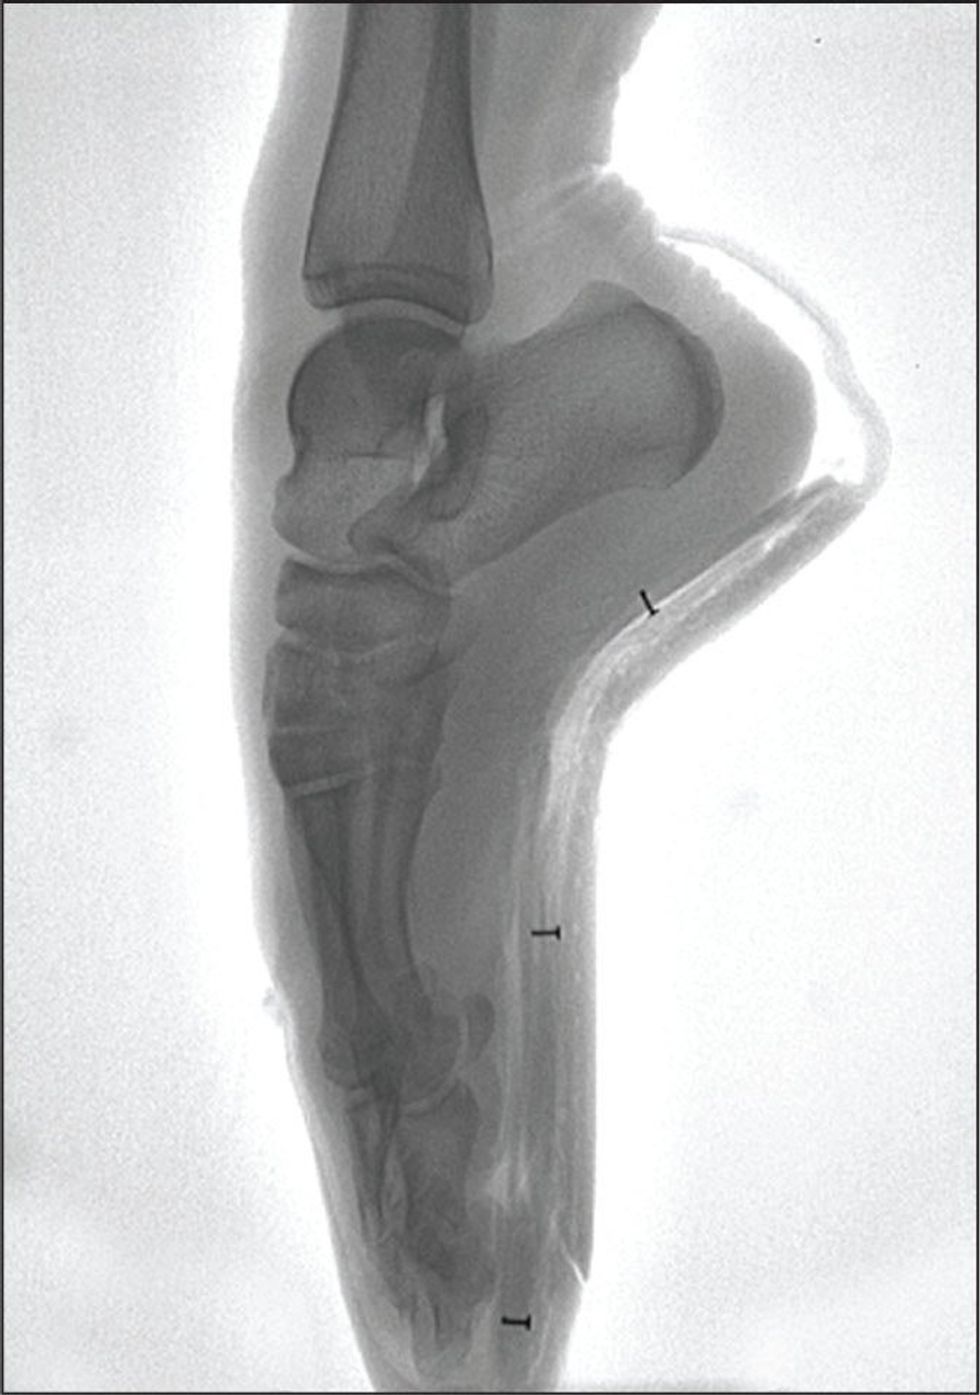

I was just standing there, in the middle of the floor -- literally just doing an arm movement. It was during a stupid, simple Mary Poppins dance. My ankle buckled and within a matter of a few seconds, my entire body collapsed over my foot. I tried to get up, but the agonizing pain prevented me from using my legs. My dance teacher panicked and called my parents who took me right to the emergency room. After spending the night there and basically high on pain meds, they concluded I had snapped my fourth and fifth metatarsals in half. They told me I wouldn’t be able to walk without a huge medical boot for six weeks.

My foot is still pretty messed up from that day, a little over two years ago. It aches after walking long distances or during an intense ballet class. Although I continued dancing, I had to abandon my dream of continuing my pointe career...it would just be too much.

For my follow-up x-ray a few weeks later, I was pretty nervous. I went to the children’s hospital and had to lay down in a dark room for a while. The ceiling was painted with tiles that some of the little patients drew, all positive, jubilant, and calming images. The one I was staring at was painted by a little girl that read the word ‘HOPE’ in big pink letters. The O was a smiley face. I started at it the entire time, hoping for the best. Hope is my favorite word and that tile really made me feel better throughout this entire journey. To just have some hope!